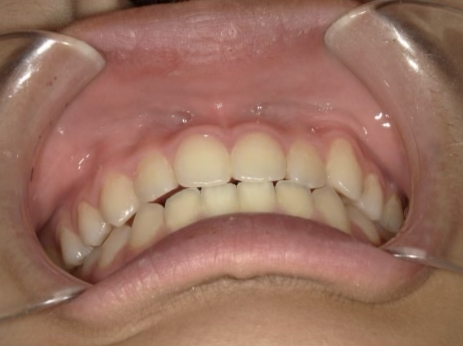

治療中④ 小4:10y1m

左上3が八重歯で萌出中